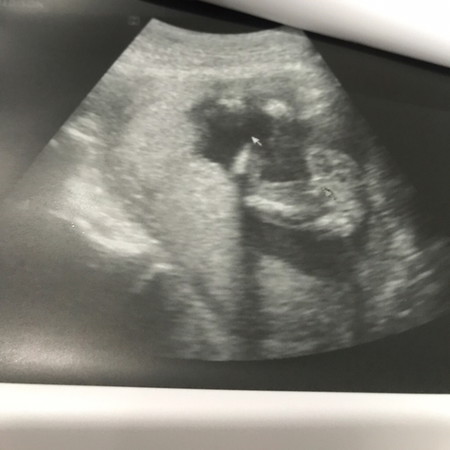

วันนี้ไปซาวด์เพศ 16w4d คุณหมอบอกคุณได้ลูกสาว ตัวแม่เองกะดูไม่เป็น! แต่ดีใจมากๆ หวังว่าคุณหมอจะไม่ซาวด์พลาด ตื่นเต้นที่สุดๆ คุณแม่ท่านอื่นดูภาพซาวด์ออกมั้ย??ช่วยยืนยันให้ชื่นใจหน่อยค่ะ